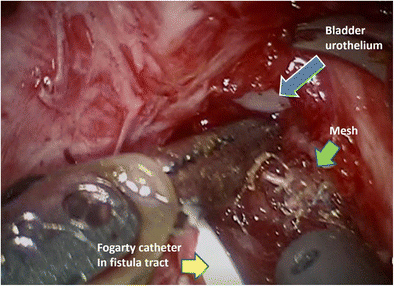

Since there was no obvious erosion but urothelium friability, we recommended close surveillance with cystoscopies every 6 months and vaginal estrogen. A year later, the patient presented with vaginal bleeding, foul discharge after intercourse, urine debris, and bladder pressure. She had granulation tissue along the posterior vaginal wall and adequate vaginal support. She had stopped the vaginal estrogen and was restarted. Examination under anesthesia and cystoscopy performed for surgical planning diagnosed a vesicovaginal fistula at the prior friable urothelium site with a suture visible. Additionally, she had a posterior vaginal wall mesh exposure below the granulation tissue, which was easily removed, and the muscularis and epithelium were approximated. A flexible sigmoidoscopy ruled out rectovaginal fistula. Afterwards, a CT urogram was negative for ureterovaginal fistula and inflammation. Finally, she underwent a robotic-assisted laparoscopic vesicovaginal fistula repair with omental flap, cystoscopy with bilateral ureteral stents, and suprapubic tube placement. A Fogarty catheter (a common cardiac catheter) was placed through the fistula to better identify it during the fistula repair (Figs. 1 and 2). The entire mesh was not resected. At her 4-week postoperative visit, she denied leakage, discharge, or discomfort.